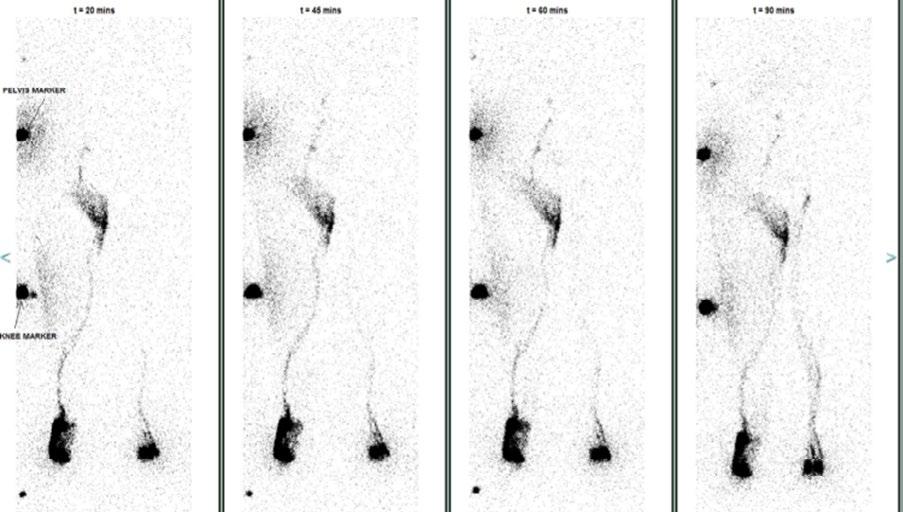

Issuu converts static files into: digital portfolios, online yearbooks, online catalogs, digital photo albums and more. Sign up and create your flipbook.